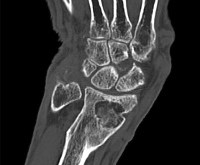

КТ лучезапястного сустава

КТ лучезапястного сустава назначают пациентам для диагностики травматических повреждений. Во время сканирования могут быть обнаружены переломы костей запястья, дистальной лучевой и локтевой костей, переломы запястья и вывихи костей запястья. Кроме того, с помощью исследования можно определить давние посттравматические изменения в костном и хрящевом аппарате. Томография показана при подозрении на синдром запястного канала. Методика эффективна при диагностике воспалительных процессов - артрита, остеомиелита. Используя компьютерную томографию, можно оценить обширность патологического очага и распространенность изменений в окружающей ткани. Кроме того, этот метод используется для обнаружения гноя, крови в суставной полости.

КТ является информативным для определения доброкачественных и злокачественных опухолей. Получение послойных изображений позволяет диагностировать новообразования небольшого размера, не сопровождающиеся клиническими проявлениями, выявлять метастазы. Сканирование используется для выявления дегенеративно-дистрофических изменений, в частности артроза, остеопороза. Показанием для исследования является подозрение на врожденные или приобретенные аномалии структуры сустава. В качестве дополнительного диагностического метода рентгеновский метод используется при ревматологических заболеваниях, системных поражениях соединительной ткани, при подготовке к операции или для контроля эффективности хирургического вмешательства.

КТ лучезапястного сустава похожа по своей эффективности на МРТ, но последняя предполагает использование магнитного поля и радиоволн. С помощью компьютерного сканирования можно визуализировать элементы кости как можно более подробно, в то время как магнитно-резонансная томография предоставляет исчерпывающую информацию о состоянии мягких тканей. Еще одним преимуществом МРТ является отсутствие рентгеновского облучения. Тем не менее, КТ является более доступным с точки зрения стоимости, поэтому он используется гораздо чаще. Процедура может быть назначена даже в детстве, если есть трудности в диагностике.